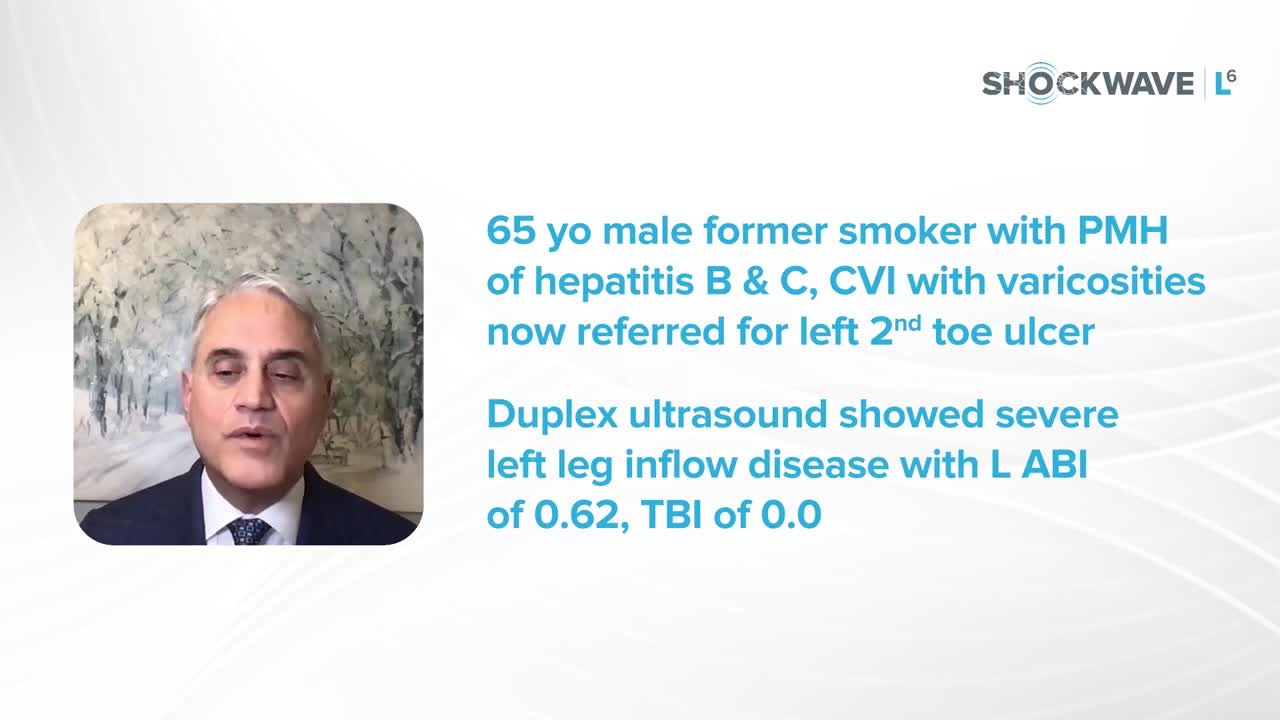

Dr. Charles Briggs Discusses Shockwave L6 and Its Critical Role in Treating Heavily Calcified Vessels

IVL cracking the calcium conundrum in PAD

Peripheral IVL from the Renals to the Toes